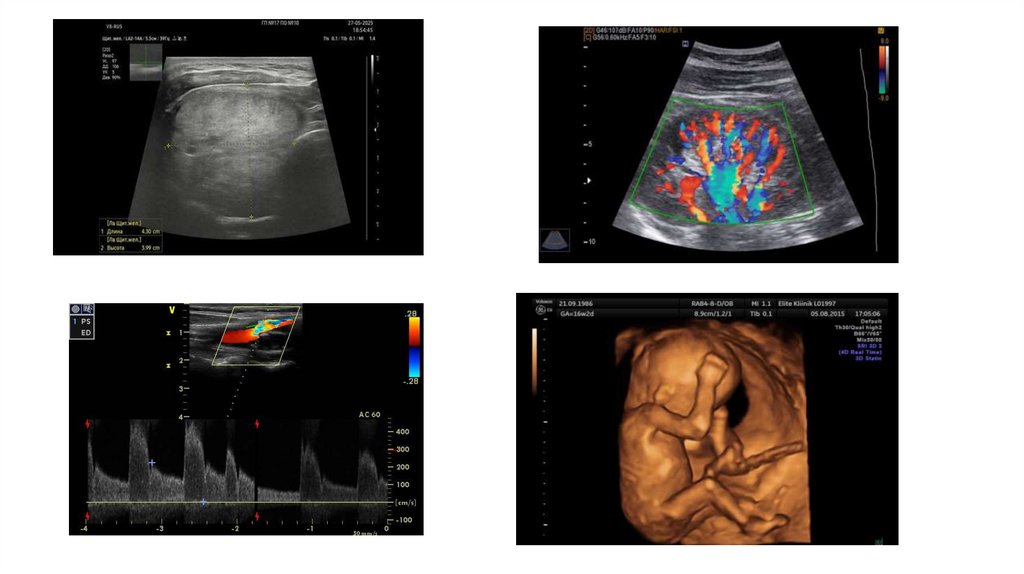

УЗИ ЩИТОВИДНОЙ ЖЕЛЕЗЫ

16. УЗИ ЩИТОВИДНОЙ ЖЕЛЕЗЫ

10. Методы ультразвуковой диагностики:

Эхография;

Допплерография

Триплексное исследование;

Трехмерное исследование (объемная визуализация);

Эластография;

Ультразвуковое исследование с применением контрастирующих

препаратов;

• Мультимодальная визуализация.